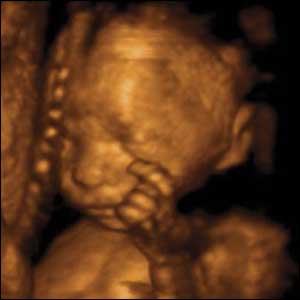

15 týdnů, 11 cm

Mozek pozorovaného dítěte je vyvinutý natolik, že je schopno uvědomit si části svého těla. Může se dotknout prsty tak, že je cítí.